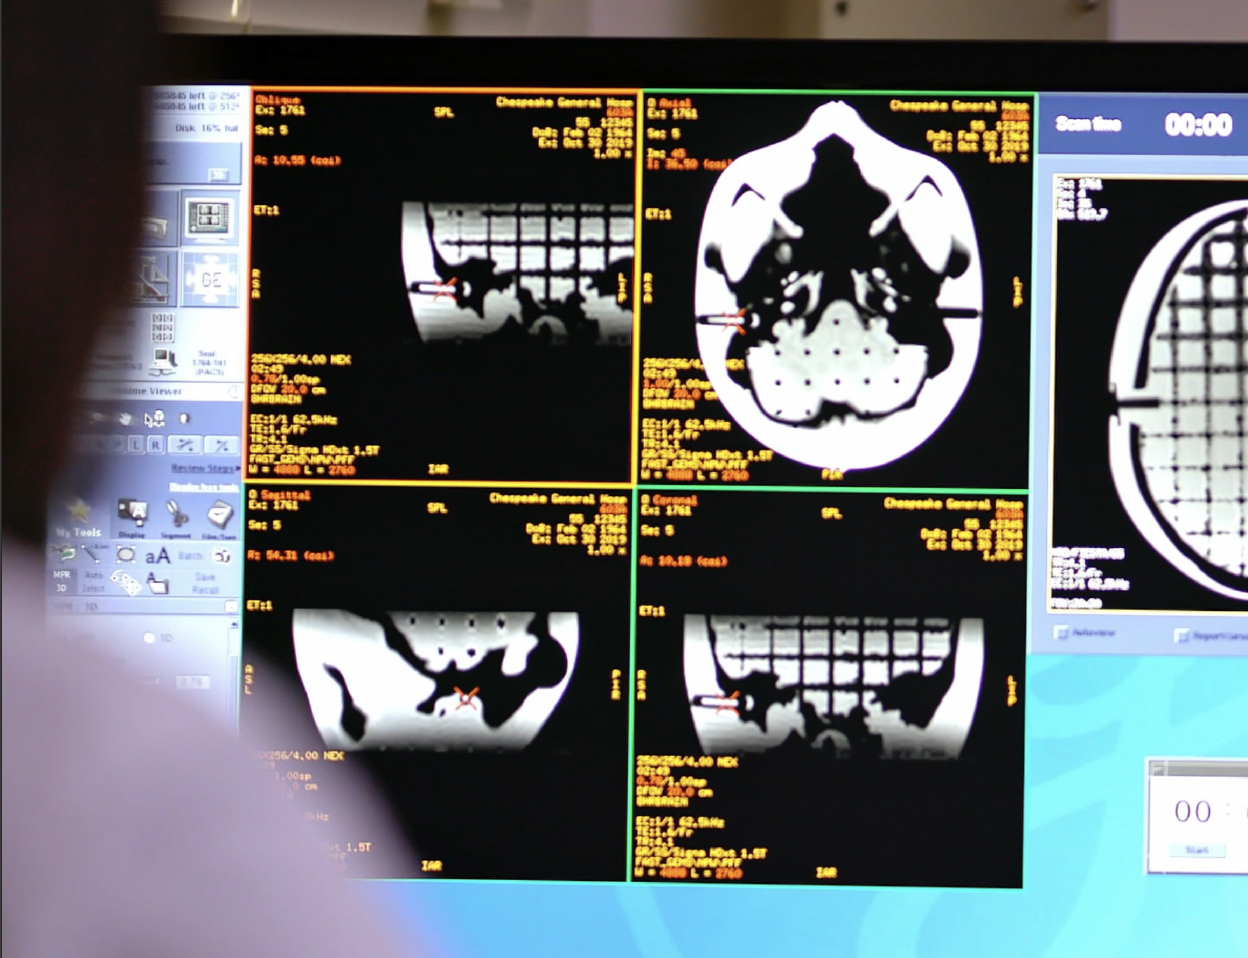

The SRS MR Distortion Phantom is an anthropomorphic SRS QA phantom designed to assess MR image distortion in stereotactic radiosurgery planning.

The SRS MR Distortion Phantom is useful for verifying image fusion and deformable image registration algorithms used in various treatment planning systems. The tissue equivalent, anthropomorphic design closely matches clinical imaging scenarios.

Tissue Equivalent, Anthropomorphic Head

The skull is made from a plastic-based trabecular bone substitute, and the interstitial and surrounding soft tissues are made from a proprietary signal-generating water-based polymer. The entire phantom is encased in a clear plastic shell to protect gel from desiccation. Specially designed pads allow fixation with any stereotactic frame or mounting devices for end-to-end

testing. The phantom is also suitable for frameless SRS QA.

The entire inter-cranial portion of the skull volume is filled with an orthogonal 3D grid of 2.5 mm diameter cross-like shaped rods spaced 10 mm (I-S), 10.5 mm (AP), and 11 mm (L-R). Extra material added in the grid intersections increases grid signal. Five extended axis-rods intersect at the reference origin of the grid. The end of each extended axis is fitted with CT/MR markers allowing for accurate positioning with lasers and co-registration of CT and MR image sets.

The phantom contains air voids on both sides that replicate ear canals. These voids are utilized to assess common distortions encountered in clinical settings.

The SRS MR Distortion Phantom can be imaged using X-ray, CT and MR. It images well with all MRI sequences tested to date, including T1 weighted, T2 weighted, 3D Time of Flight, MPRAGE and CISS.